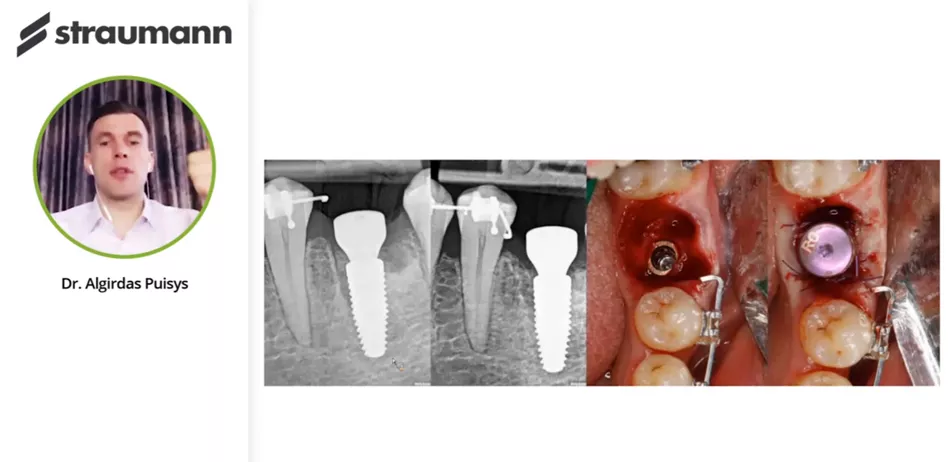

Campus Live Webinar with Dr. Algirdas Puisys: Crestal bone stability after immediate implant placement in molars

Achieving an optimal result by replacing a single missing tooth with an implant immediately after tooth extraction is a demanding procedure even in this high-technology time, and especially in the molar area.

• Immediate implant placement in molar area

• 3D positioning of the implant